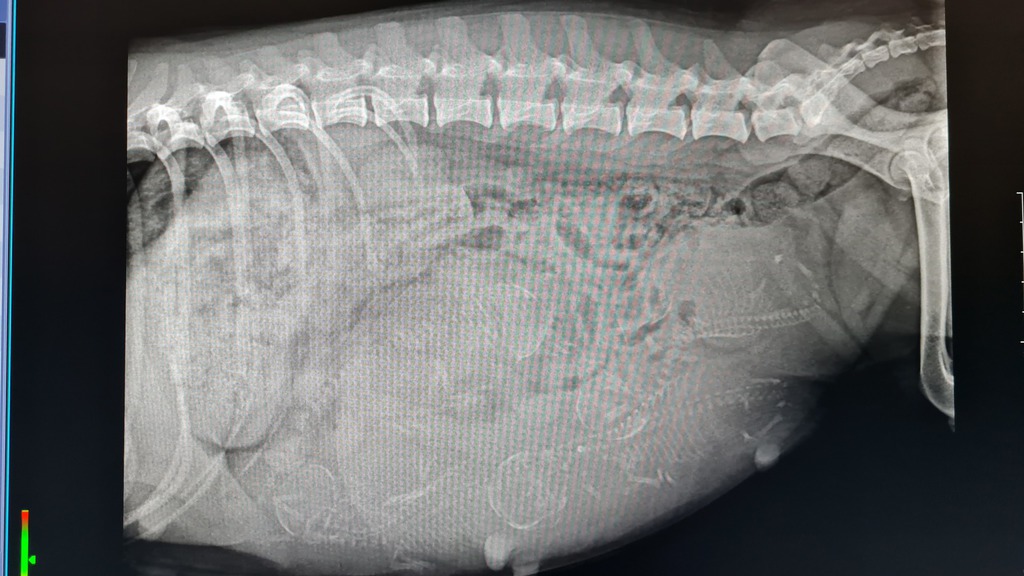

Gina hatte sich relativ schnell auf ihren Wurf vorbereitet und am Sonntag dem 14.07.2024 ihre Welpen problemlos zur Welt gebracht.

Es sind 2 Hündin und 3 Rüden.